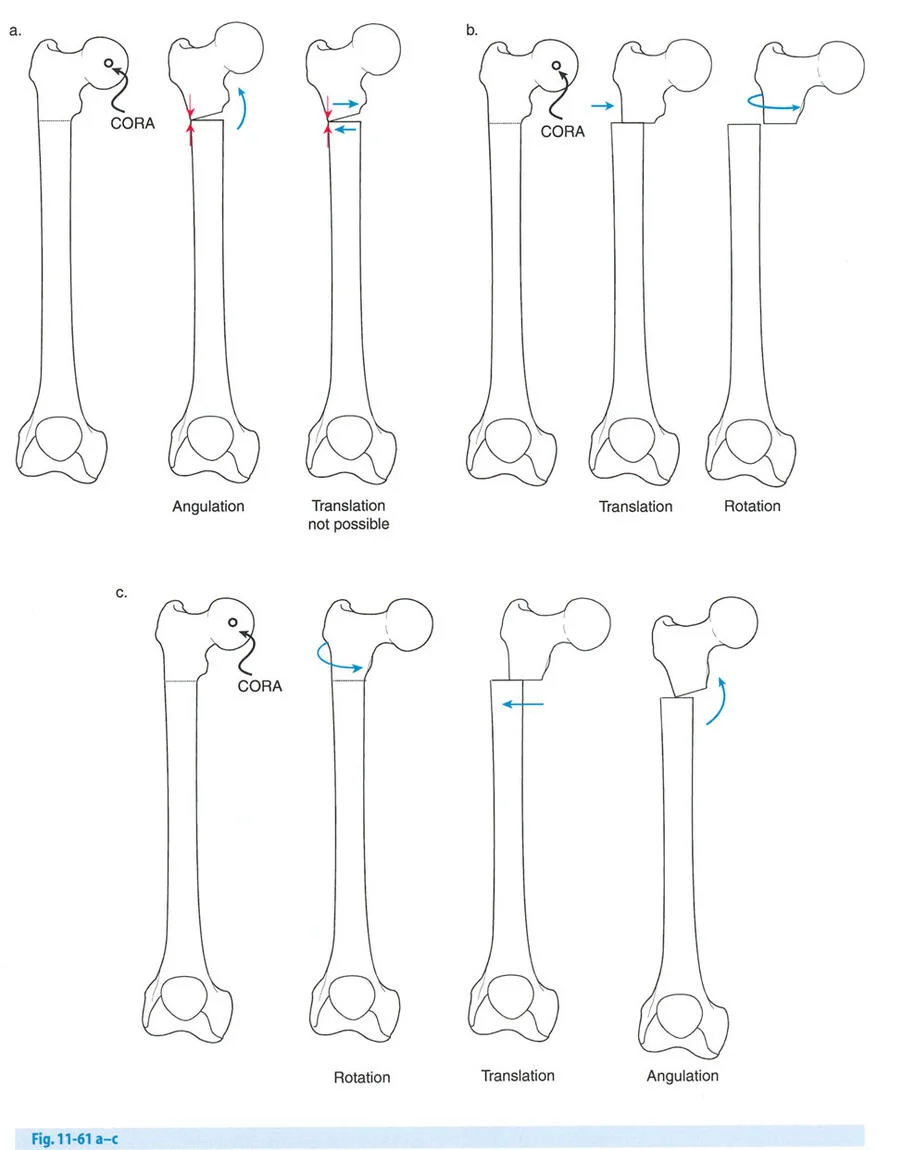

هذا الدليل الشامل يستعرض الاعتبارات الحاسمة لتطبيق الأجهزة، وتحديد مواضع المفاصل الاصطناعية (المفصلات)، وآليات الشد، والتسلسل الاستراتيجي للتصحيحات التدريجية. سواء كان الجراح يستخدم مثبتات إليزاروف الدائرية التقليدية، أو أنظمة الهيكسابود الحديثة (مثل جهاز تايلور الفراغي Taylor Spatial Frame)، أو المثبتات أحادية الجانب، فإن القواعد الهندسية التي تحكم مركز دوران الانحراف (CORA)، ومحور تصحيح الانحراف (ACA)، وانحراف المحور الميكانيكي (MAD) تظل مطلقة ولا تقبل الخطأ.

المفصلات القريبة من المفصل وقواعد قطع العظم (Osteotomy Rules)

عند التعامل مع التشوهات الواقعة بالقرب من خط المفصل - مثل التقوس الشديد في الجزء العلوي من الساق (مرض بلونت) أو التشوه الفحجي في الجزء السفلي من عظم الفخذ - يصبح وضع الجهاز مقيدًا هندسيًا. إن المتطلبات البيولوجية للحفاظ على كبسولة المفصل، وتجنب وضع الأسلاك داخل المفصل، ومنع التهاب المفاصل القيحي، غالبًا ما تجبر الجراح على وضع الحلقة المرجعية على مستوى مختلف تمامًا عن مركز دوران الانحراف (CORA) الفعلي.

تحدي مركز دوران الانحراف (CORA) القريب من المفصل

لمطابقة مفصلة المثبت الخارجي مع المستوى الدقيق لمركز دوران الانحراف (CORA)، يجب غالبًا بناء المفصلة فوق أو تحت مستوى الحلقة الفعلية. يُعرف هذا في مبادئ بالي باسم تجميع المفصلة القريبة من المفصل (juxta-articular hinge assembly).

إذا كان مركز دوران الانحراف (CORA) يقع بالقرب من خط المفصل، فإن وضع حلقة إليزاروف القياسية عند هذا المستوى بالضبط مستحيل دون انتهاك مساحة المفصل أو شد الهياكل الكبسولية الحيوية. لذلك، يتم تثبيت الحلقة المرجعية بالعظم الكثيف أو العظم الطويل المتاح، ويتم بناء آلية المفصلة باستخدام قضبان ملولبة، ولوحات توصيل، ودعامات. ثم يتم "إنزالها" (أو رفعها) لتتطابق تمامًا مع مركز دوران الانحراف (CORA) الهندسي الحقيقي.

قواعد بالي لقطع العظم (Osteotomy Rules) في وضع الأجهزة

فهم قواعد بالي لقطع العظم أمر لا غنى عنه لتخطيط الإطار:

- قاعدة قطع العظم 1: عندما يمر قطع العظم ومحور تصحيح الانحراف (ACA) كلاهما عبر مركز دوران الانحراف (CORA)، فإن نهايات العظم ستنحرف دون ترجمة (انزياح). يتم استعادة المحور الميكانيكي، وتظل نهايات العظم متقاربة تمامًا، مما يخلق تصحيحًا كلاسيكيًا "إسفينيًا مفتوحًا" أو "إسفينيًا مغلقًا".

- قاعدة قطع العظم 2: عندما يمر محور تصحيح الانحراف (ACA) عبر مركز دوران الانحراف (CORA)، ولكن يتم إجراء قطع العظم على مستوى مختلف (غالبًا بسبب ضعف جودة العظم عند CORA أو مشاكل في الجلد)، فإن نهايات العظم ستنحرف وتخضع لترجمة محسوبة ومقصودة لإعادة محاذاة المحور الميكانيكي.

- قاعدة قطع العظم 3: (للاكمال) عندما يمر قطع العظم عبر مركز دوران الانحراف (CORA)، ولكن يتم وضع محور تصحيح الانحراف (ACA) خارج CORA، سيتم إنشاء تشوه ترجمة جديد، وهو خطأ شائع في وضع المفصلات غير المخطط له جيدًا.

في المنشآت القريبة من المفصل، غالبًا ما نعتمد على قاعدة قطع العظم 2. نظرًا لأنه لا يمكننا قطع العظم بأمان عند خط المفصل تمامًا (مركز دوران الانحراف CORA)، فإننا نقطع العظم في مستوى أدنى في منطقة الميتافيسيس. بعد تحقيق التصحيح الزاوي عبر المفصلات (محور تصحيح الانحراف ACA)، يتم إعادة محاذاة خطوط المحور الميكانيكي بشكل مثالي، ولكن نهايات العظم في موقع قطع العظم تتحرك بالنسبة لبعضها البعض.

قيود الأسلاك والدبابيس في القاعدة 2

لتحقيق هذه الترجمة الضرورية والمقصودة بسلاسة باستخدام إطار دائري كامل الأسلاك، يلزم استخدام أسلاك الزيتون المعاكسة (counter-opposed olive wires). تعمل أسلاك الزيتون كقوى سحب ديناميكية، تسحب قطعة العظم على طول الحلقة أثناء فتح المفصلات. بدون أسلاك الزيتون، سيبقى العظم ثابتًا بينما تتحرك الحلقة عبر الأنسجة الرخوة، مما يسبب نخرًا شديدًا في الجلد.

على العكس من ذلك، إذا تم استخدام دبابيس نصفية (مسامير شانز)، فإنها تقيد العظم بطبيعتها بالحلقة. نظرًا لأن الدبابيس النصفية هي أذرع صلبة (مثبتة من طرف واحد بالحلقة ومغروسة في العظم من الطرف الآخر)، فإنها لا تسمح للعظم بالانزلاق على طول محور السلك. هذا يجعل أسلاك الزيتون غير ضرورية للترجمة في منشآت الدبابيس النصفية، ولكنه يتطلب من الجراح التأكد من أن الدبابيس النصفية قوية بما يكفي (عادةً دبابيس بقطر 5 مم أو 6 مم مطلية بهيدروكسي أباتيت) لتحمل لحظات الانحناء الناتجة عن الترجمة.